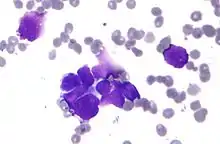

| Micrograph of a lung primary small cell carcinoma, a type of carcinoma. The clustered cancerous cells consist primarily of nucleus (purple); they have only a scant rim of cytoplasm. The surrounding pale staining, discoid cells are red blood cells. Cytopathology specimen. Field stain. | |

- Small cell carcinoma

- Cells are usually round and are less than approximately 3 times the diameter of a resting lymphocyte and with little evident cytoplasm. Occasionally, small cell malignancies may themselves have significant components of slightly polygonal and/or spindle-shaped cells.[8]